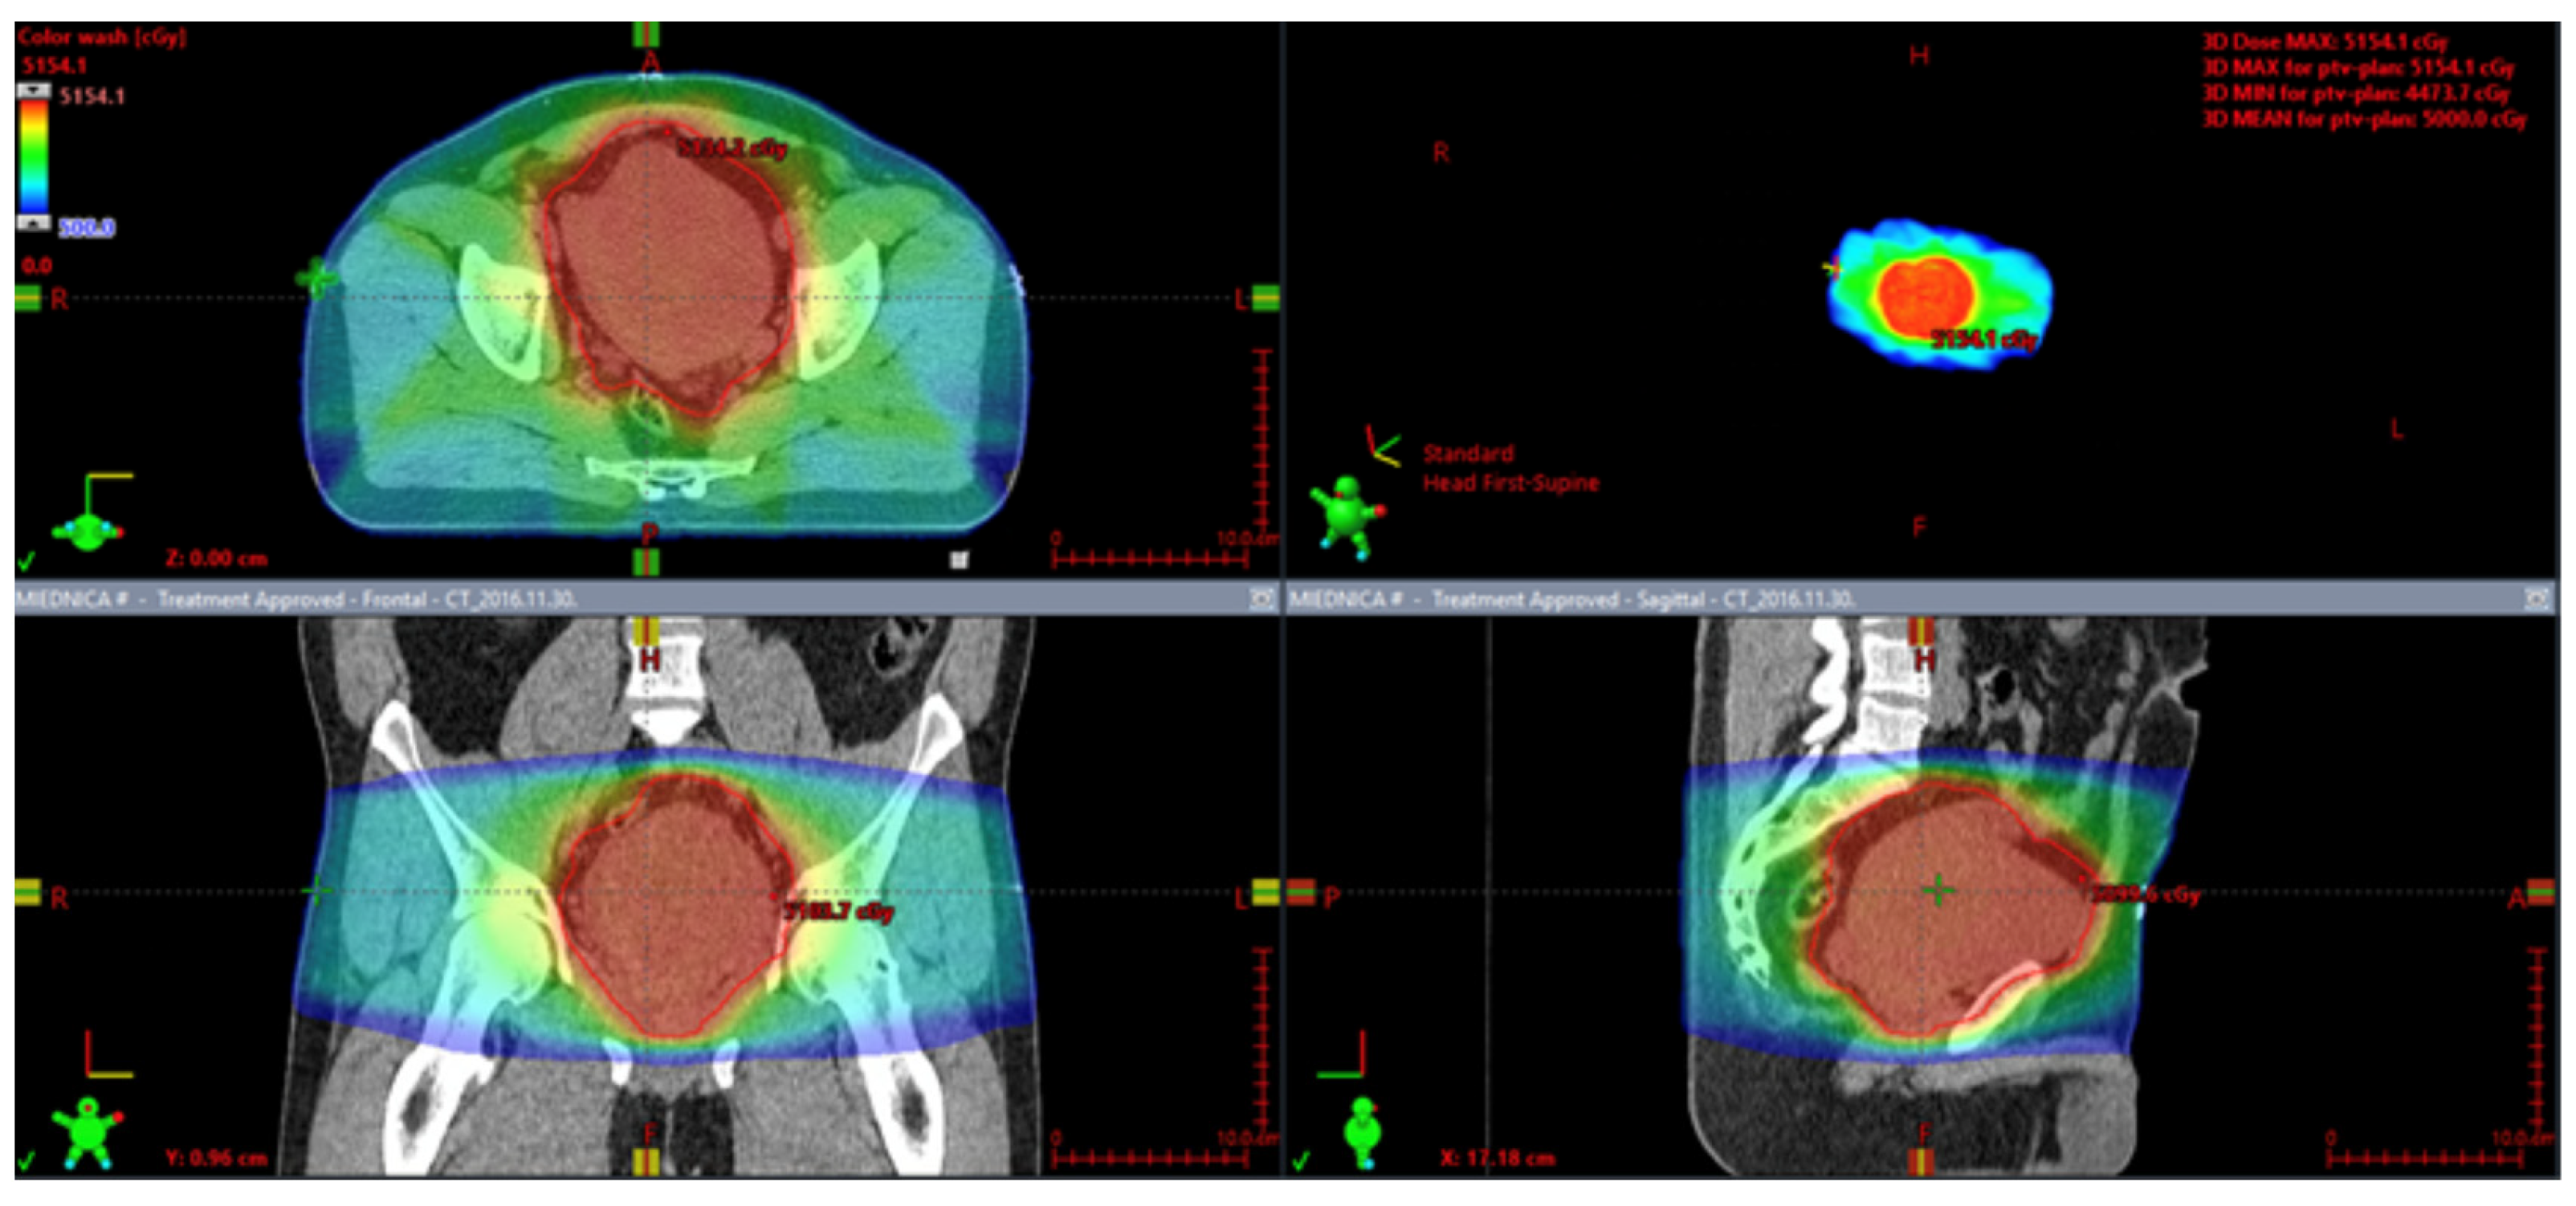

Figure 9.

Stereotactic radiotherapy for a metastatic solitary fibrous tumor.

Treatment of metastatic disease is very challenging. To date, no clear guidelines have been published [167], while in our clinic all patients are subject to a multidisciplinary team decision according to national treatment guidelines [184]. Most commonly, anthracyclines are used in the first line of treatment, while trabectedin, dacarbazine, and ifosfamide are used in subsequent lines [167]. Doxorubicin monotherapy is the preferred first-line treatment [167]. In selected cases in the first line of treatment, the combination of doxorubicin and dacarbazine is preferred [185]. Furthermore, an objective response has been reported in patients with recurrence and lung metastasis treated with doxorubicin and gemcitabine in combination. In this case, radiological follow-up showed PR [48]. In one of the analyses of advanced unresectable metastatic tumors or potentially resectable cases, patients received chemotherapy regimens based on doxorubicin or gemcitabine [186], but an objective response was not achieved. However, in 89% of the participants, SD was reported [186]. In another study of locally advanced or metastatic cases, patients received anthracycline monotherapy or in combination with ifosfamide [187]. In 20% and 27% of the cases, PR/SD were observed, respectively. However, the rest of the tumors progressed [187]. Comparable results were obtained in other analyses, with doxorubicin, ifosfamide, palifosfamide, brostallicin, vinorelbine, and paclitaxel alone or in combination with carboplatine. Median progression-free survival was 5.2 months [188]. Stacchiotti et al. analyzed 12 patients with advanced (malignant or dedifferentiated) SFTs who received combined treatment based on doxorubicin (75 mg/mq, iv bolus) and dacarbazine (800 mg/mq, intravenously over 60 min, two days), every three weeks. The median OS and PFS were 19 months (range 9–44+) and six months (range 2–32), respectively. Furthermore, the median PFS for malignant tumors was six months, while for dedifferentiated SFT it was four months longer [189]. On the contrary, De Vito et al. showed that patients with primary metastatic disease have worse OS and conventional chemotherapy is not associated with long-term positive effects [190]. Furthermore, surgical cytoreduction in combination with hyperthermic intraperitoneal chemotherapy has been tested in patients with recurrent SFTs with liver dissemination. Subsequently, the patient developed lung metastases and was treated with palliative chemotherapy to achieve SD [191]. At the same time, a valuable method for the management of metastatic SFTs could be high-dose ablative radiotherapy or metastasectomy, as shown by multiple sarcoma centers. Two recent studies analyzed large cohorts of patients with soft tissue and bone sarcomas who were treated with stereotactic radiotherapy (Figure 9). These groups included 10 patients with SFT [184,192]. Both studies confirmed the high local efficacy of stereotactic radiotherapy. An example of stereotactic radiotherapy administered for a metastatic SFT is presented in Figure 5. The patient received 40 Gy in 8 Gy fractions for the gross tumor volume and 25 Gy in 5 Gy fractions for the elective volume of the affected vertebrae. In cases progressing with metastases after excision of the primary tumor, metastasectomy may be performed [168,193]. However, this carries a risk of death within months, essentially if no subsequent adjuvant systemic therapy is used [168]. A case of a patient with a primary SFT located in the abdominal cavity and multiple liver metastases treated with surgery and radioembolization has been reported [194]. Palliative radiotherapy for metastatic disease with a total dose of 39 Grays was shown to be beneficial. Haas et al. showed that it positively affects both the five-year local control and OS at 62.5% and 54.2%, respectively [180].